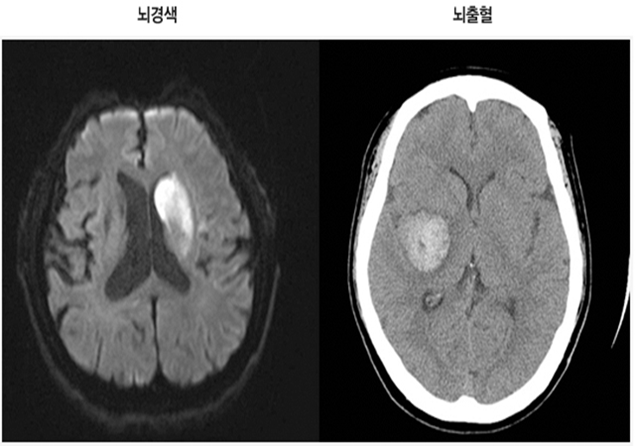

뇌졸중 (중풍)

뇌혈관 이상으로 갑자기 발생하며, 손발의 마비 증상 및 호흡 곤란 등의 증상이 나타나는 질환입니다.